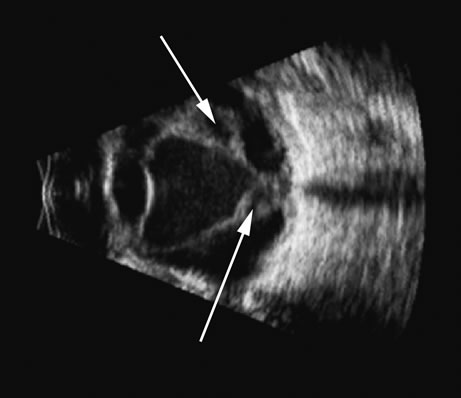

Fig. 12. Scleritis of the posterior pole produces an accentuation of the Tenon's surface posterior to the sclera and is commonly traceable to the meninges as they pass posteriorly along the optic nerve. This accentuated reflective “space” is often called a T-sign (arrow).

Inflammation of the vitreous can produce cellular and fibrotic conglomerates that produce echoes similar to those of hemorrhage. Differentiation is usually made on clinical grounds but may be suggested by the presence of inflammation-induced swelling of the choroid and sclera, and by the presence of a fluid layer between Tenon's capsule and the orbital fat, which is commonly seen in scleritis (Fig. 12).12 Other conditions, such as hypotony, produce identifiable thickening of the choroid and sclera. Hypotony in its later stages also produces the characteristics of the “pre-phthisic” eye, namely, shortened axial length and cyclitic membrane formation.13